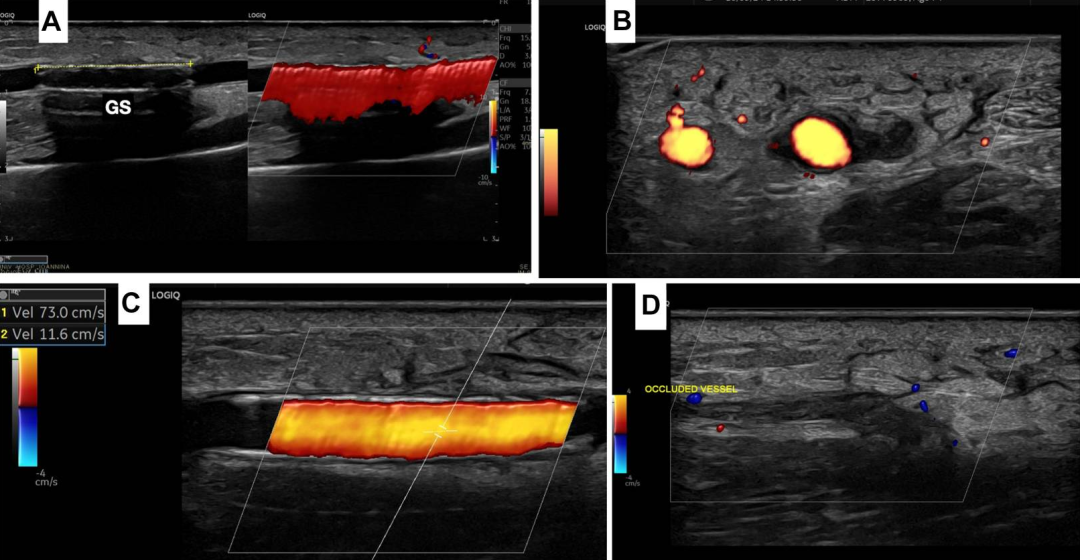

临床怀疑AVF,前臂超声(图3)迅速确认了AVF的诊断。

图3.桡动静脉瘘的基线超声图像

(A)桡动脉(RA)与静脉(RV)之间的瘘口(箭头);(B)RA和RV的横断面超声图像;(C)瘘口的湍流;(D)RA侧的瘘口;(E)桡静脉血流“动脉化”及彩色伪影。